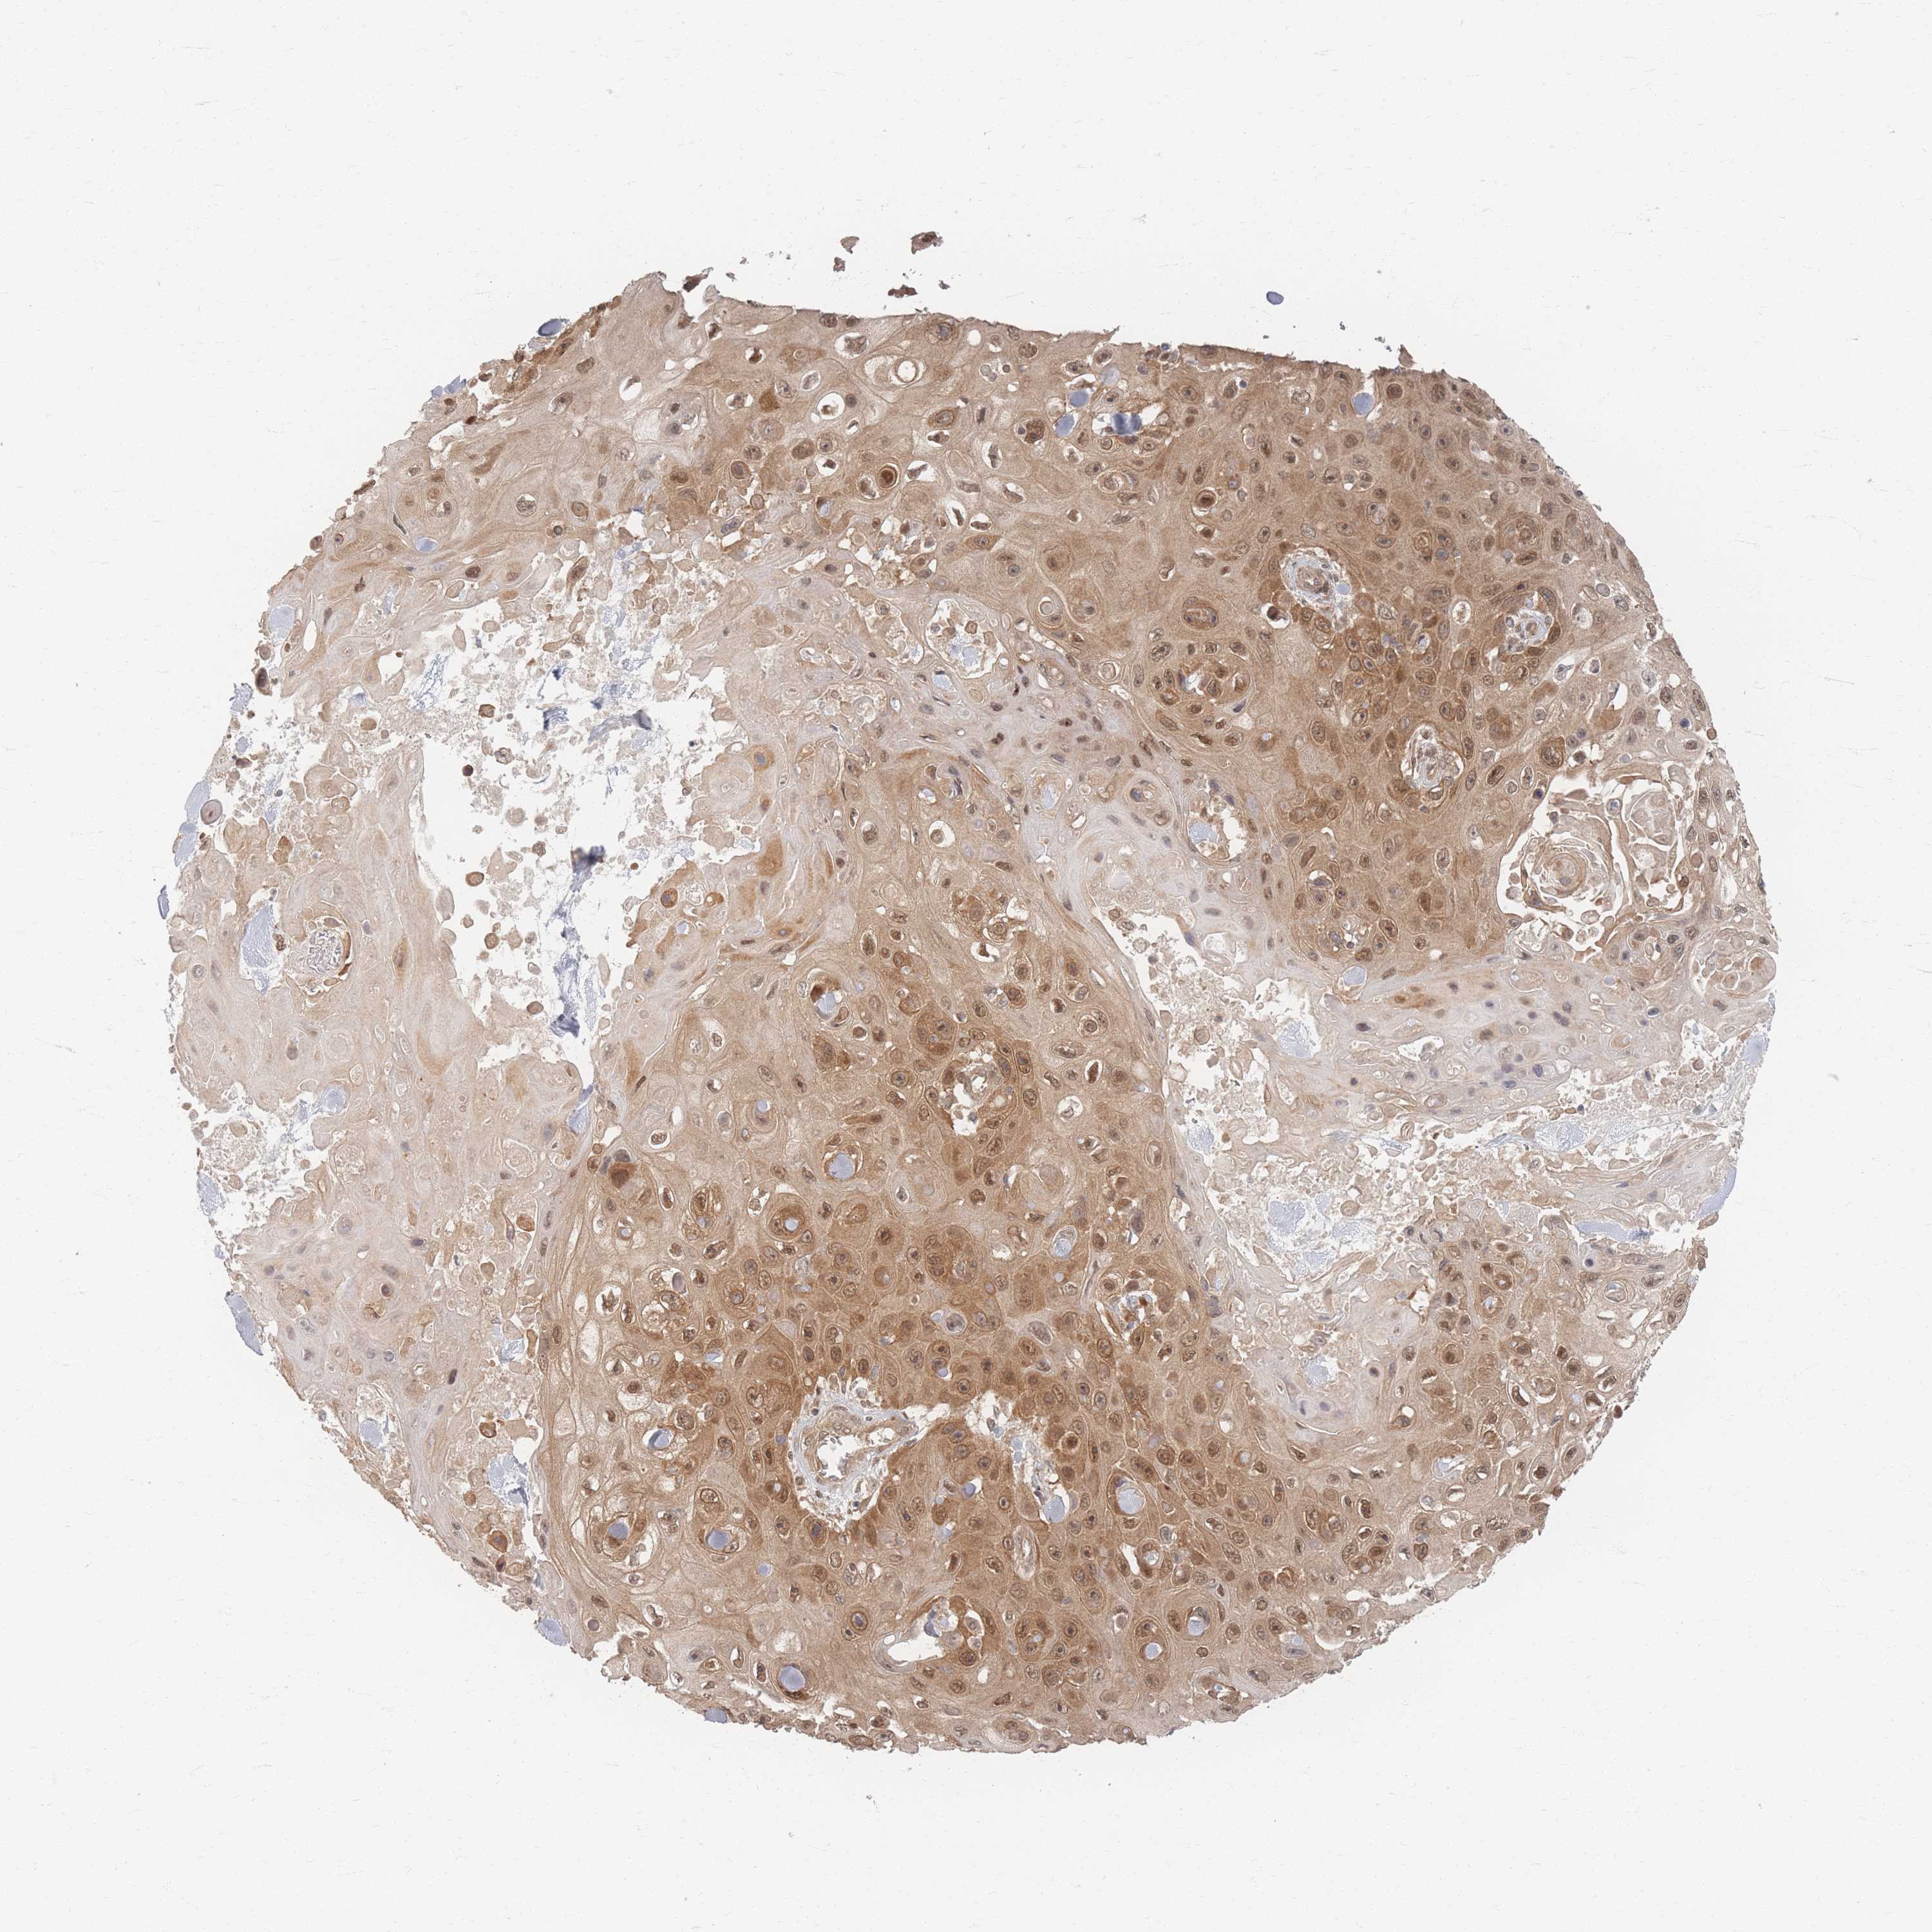

CANCER SKIN CANCER Show tissue menu

Basal cell and squamous cell cancer

SKIN CANCER - Protein expressioni

A mouse-over function shows sample information and annotation data. Click on an image to view it in a full screen mode. Samples can be filtered based on level of antibody staining by selecting one or several of the following categories: high, medium, low and not detected. The assay and annotation is described here.

Each image is clickable and will lead to virtual microscopy that enables deeper exploration of all samples and also displays staining intensity scores, fraction scores and subcellular localization as well as patient and tissue information for each sample.

Antibody HPA040512

Antibody HPA044220

Staining

High

Medium

Low

Not detected

Intensity

Strong

Moderate

Weak

Negative

Quantity

>75%

75%-25%

<25%

None

Location

Nuclear

Cytoplasmic/membranous

Cytoplasmic/membranous,nuclear

Basal cell carcinoma

Squamous cell carcinoma, NOS

Squamous cell carcinoma, metastatic, NOS